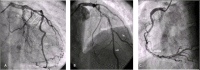

Multivessel Woven Coronary Artery Disease

Woven coronary disease is a rare pathology with unknown etiology. Although initially considered benign, recent publications report myocardial ischemia caused by the affected vessel. Since most patients are asymptomatic, long-term follow-up to understand its behavior is mandatory. We report a multivessel woven disease case with documented ischemia that was submitted to coronary artery bypass grafting and remained asymptomatic for two years of follow-up.